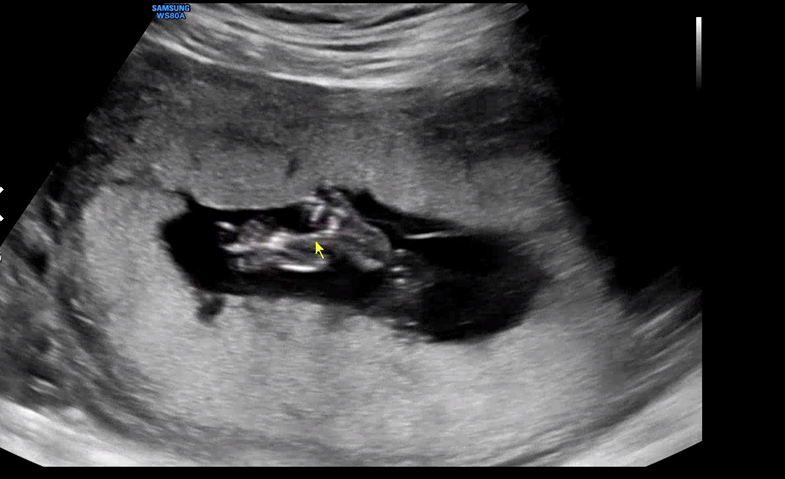

꼬물꼬물 움직이는 아기를 관찰하다 발가락도 이렇게 예쁘게 생긴 걸 보여주셨다.

손을 입에 대었다 주먹을 꽉 쥐었다 열심히 움직이는 우리 아기. 아기가 잘 움직이는 건 너무 좋은 증상이라도 원장님이 말씀해주셨다. 16주부터는 대략적인 태아의 체중을 측정할 수 있는데 155g으로 무럭무럭 자라고 있다. 임신이라고 크게 뭘 하지 않는데도 혼자서 너무 잘 자라주고 있어서 기특하다.